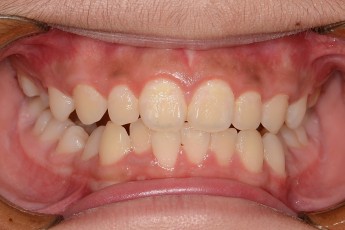

BEFORE & AFTER

- 덧니교정